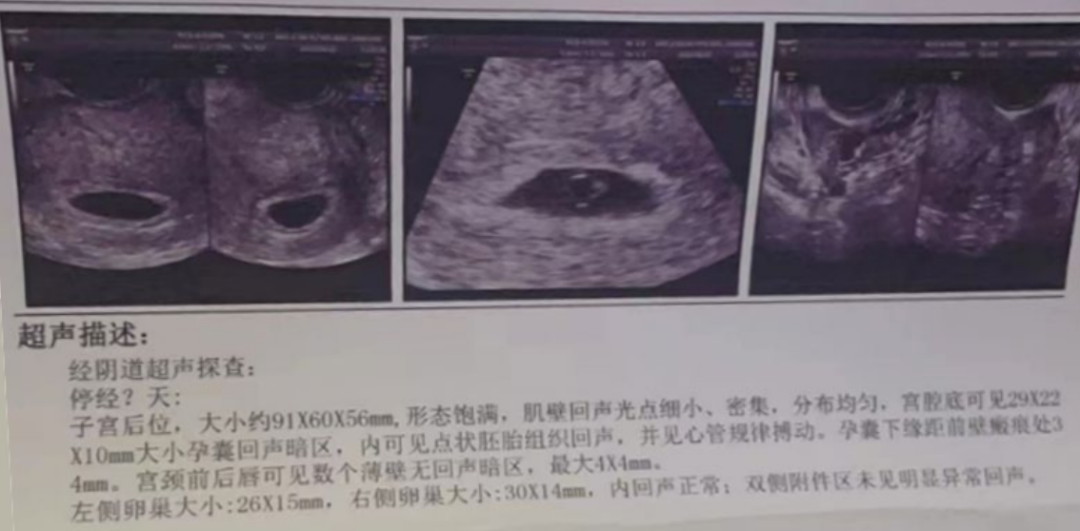

胎心胎芽出现

怀孕第 6 周,超声检查清晰看到胎心胎芽,胚胎发育状况良好。